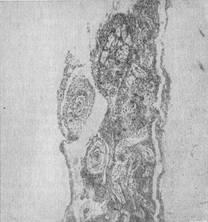

![]() Рис. 8. Хронічний спинальний (переважно продуктивний) туберкульозний лептопахименингит. Різко виражені зміни в оболонках; спаяние корінців, освіта туберкулов, продуктивні васкуліти е різким звуженням просвіту судин оболонок. |

Мікроскопічно при туберкульозному менінгіті ексудат має серозно-фібринозний характер, закономірно піддаючись казеозного некрозу. Туберкульозні горбки мають эпителиоидное будова з наявністю гігантських клітин типу Лангханса. Поряд з цим спостерігаються горбки, майже суцільно складаються з лімфоцитів. В центральних частинах деяких горбків можна бачити, казеозний розпад.